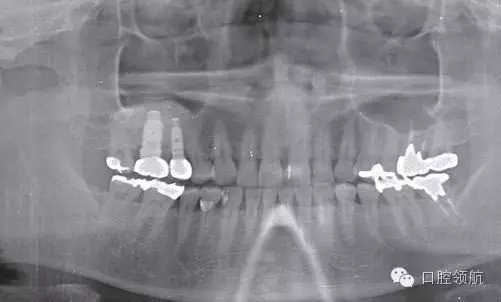

患者10年前,在外院于( 左上第六顆牙)區(qū)行上頜竇底提升術(shù)同期植入種植體,經(jīng)過10年上頜竇內(nèi)生成骨完全吸收消失了(圖1)?;颊叽舜蝸碓菏且驗猷徰? 左上第五顆牙) 不能保存,希望行種植修復(fù)治療。

圖1 術(shù)前牙片。由于上頜竇底黏膜提升植骨術(shù)而在上頜竇內(nèi)生成的骨已完全消失。